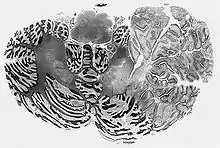

Dysplastic Cerebellar Ganglioglioma (Lhermitte-Duclos disease)

Histologically, ganglioglioma is composed of both neoplastic glial and ganglion cells which are disorganized, variably cellular, and non-infiltrative. Occasionally, it may be challenging to differentiate ganglion cell tumors from an infiltrating glioma with entrapped neurons. The presence of neoplastic ganglion cells forming abnormal clusters, the presence of binucleation and dysmorphic neurons are helpful clues favoring ganglioglioma over glioma. The glial component of ganglioglioma includes fibrillary astrocytes with varying degrees of cellular atypia. The neoplastic neuronal components are often clustered or irregularly oriented. Fibrovascular stroma confined to the neuronal component, perivascular lymphocytic infiltrates, and small foci of calcification are common, as is immunopositivity for synaptophysin, neuron-specific enolase, and chromogranin A. Elevated Ki-67 and p53 labeling index is associated with more aggressive tumor behavior in both children and adults with gangliogliomas. The rare occurrence of malignant transformation is confined to the glial cell population, and is characterized by increased cellularity and mitotic activity, endothelial proliferation, and necrosis.